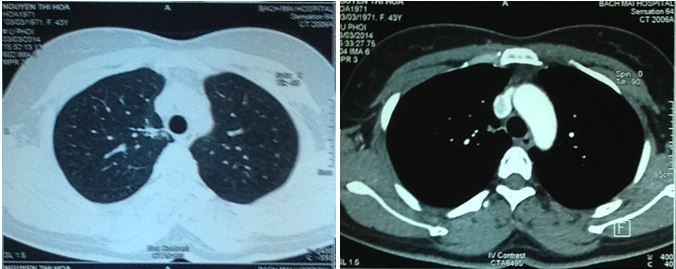

1. vChụp cắt lớp vi tính ổ bụng:

• Hình ảnh tràn dịch màng phổi phải (đã giảm hơn trước sau khi chọc tháo dịch màng phổi)

• Nang lách kích thước 20mm

• Không thấy tổn thương di căn gan, tuyến thượng thận

Hình 6: Hình ảnh trên CT ổ bụng cho thấy dịch khoang màng phổi phải (mũi tên đỏ), nang lách kích thước 20 mm (trong vòng tròn đỏ).

1. Chụp cắt lớp vi tính 64 dãy lồng ngực sau 5 tháng điều trị:

• Không thấy bất thường trên phim cắt lớp vi tính 64 dãy lồng ngực

• Không thấy hạch trung thất

Hình 10: Hình ảnh cắt lớp vi tính 64 dãy lồng ngực sau 5 tháng điều trị không thấy tổn thương ở phổi và không phát hiện hạch trung thất.